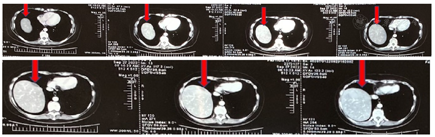

腹盆增强CT(2018年6月13日北医三院)示:肝占位病变,考虑肝转移。右侧内乳及右侧心膈角淋巴结转移(图1)。

腹盆增强核磁(2018年6月28日北医三院)示:肝占位病变,考虑肝转移(图2)。

肝转移术后复查增强核磁(2018年11月23日北医三院),见图3。